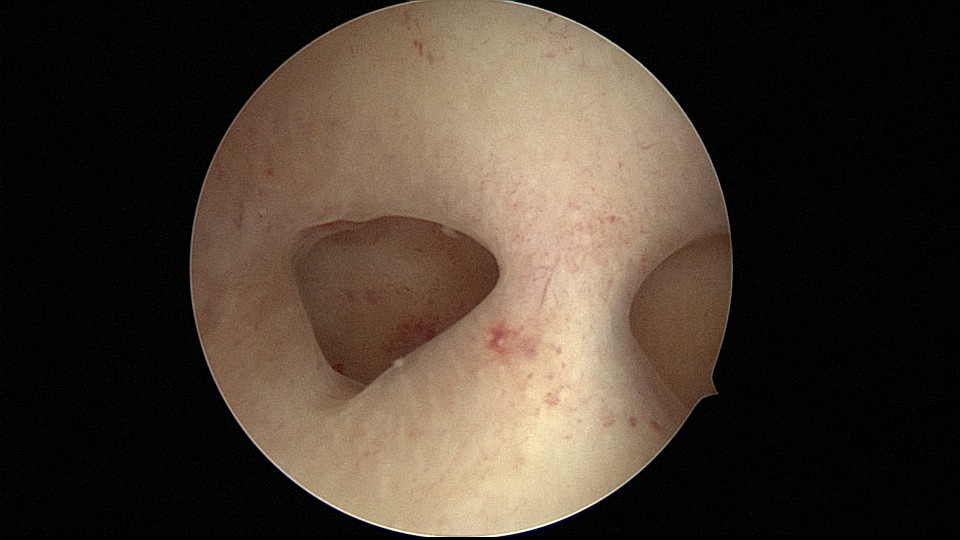

患者28岁,G1P0,2019年11月孕9周胎停1次,药流清宫,术后月经量逐渐减少,淋漓不净。外院B超发现宫腔粘连,2021年6月初宫腔镜探查,宫腔两侧及右侧宫角粘连,单级电针分粘,恢复宫腔形态,显露双侧输卵管开口(术中图像采集系统突发故障,分粘及分粘后图片未采集到)。2021年6月底宫腔镜二探取球囊,宫腔形态正常,双侧输卵管开口可见。2022年12月自然妊娠,足月顺产。现33岁,G2P1。